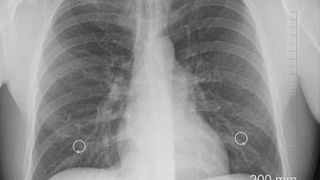

Planeta este lovită de o nouă boală. Cercetătorii susțin că este mai mortală decât COVID-19. Asia Centrală trece prin momente greu de descris. Noul tip de pneumonie ar fi ucis în acest an peste 1.700 de oameni în Kazahstan, conform oficialilor chinezi.

Cazurile au început să se înmulțească de la începutul lunii iunie. Astfel că medicii se confruntă cu sute de cazuri noi pe zi. Cele mai mari focare sunt în Atyrau, Aktobe și Shymkent.

Acesea adună peste 500 de cazuri noi și peste 30 de pacienți în stare critică, relatează oficialii ambasadei într-un comunicat pentru cetățeni.

„Această boală este mult mai mortală decât Covid-19. Departamentul de Sănătate din Kazahstan și alte agenții efectuează cercetări comparative și încă nu au definit natura acestei pneumonii", a precizat Ambasada Chineză din Kazahstan într-un comunicat pentru cetățeni.

Luna aceasta, cazurile de de pneumonie din capitala Nurusultan s-au dublat, față de anul trecut.

Șeful Departamentului de asistență medicală susține că peste 300 de persoane au fost internate în spital, în ultimele zile, iar alte victime ale bolii sunt tratate la domiciliu.